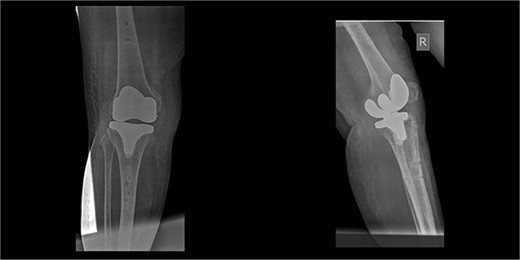

An 86-year-old female patient with a body mass index (BMI) of 31.2 presented to our outpatient department with severe right knee pain. Physical examination revealed a mechanical block of the knee, limiting its range of motion (ROM) between 10° and 55° of flexion. Plain knee radiographs showed grade 4 knee osteoarthritis (OA) in the Kellgren–Lawrence scale (Fig. 1).

The patient underwent a medial-pivot design TKA (Evolution Medial-Pivot Knee System, Microport, China). Intraoperatively, a full ROM was achieved only after extensive soft tissue and bone releases. The extension gap was limited by significant hamstring spasticity, and a proper extension gap was attained after additional anterior femoral cut. Early postoperative recovery was uneventful (Fig. 2). On the third postoperative day, the patient complained of severe knee pain accompanied by excessive swelling during kinesiotherapy. Clinical examination showed a posterior sag sign at 30° of flexion (Fig. 3). No signs of neurovascular deficit were obvious. A knee X-ray revealed posterior TKA dislocation and a small, non-displaced femoral fracture (Fig. 4). The tibial component was reducible, but redislocation occurred with the knee extended over 90°, indicative of severe instability. Laboratory investigations, including erythrocyte sedimentation rate and C-reactive protein, were normal. A knee arthrocentesis was performed with no substantial findings. Two botulinum toxin injections (200 IU) to the hamstrings were performed without improvement. Local muscle hypertonia was evaluated through a neurological examination and a brain computed tomography scan, with no remarkable findings. The patient’s history included intramedullary nailing of the right femur due to an intertrochanteric fracture 8 months before the TKA.